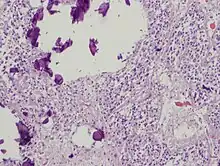

The pineal body in humans consists of a lobular parenchyma of pinealocytes surrounded by connective tissue spaces. The gland's surface is covered by a pial capsule.

The pineal gland consists mainly of pinealocytes, but four other cell types have been identified. As it is quite cellular (in relation to the cortex and white matter), it may be mistaken for a neoplasm.[19]

| Pinealocytes | The pinealocytes consist of a cell body with 4–6 processes emerging. They produce and secrete melatonin. The pinealocytes can be stained by special silver impregnation methods. Their cytoplasm is lightly basophilic. With special stains, pinealocytes exhibit lengthy, branched cytoplasmic processes that extend to the connective septa and its blood vessels. |

| Interstitial cells | Interstitial cells are located between the pinealocytes. They have elongated nuclei and a cytoplasm that is stained darker than that of the pinealocytes. |

| Perivascular phagocyte | Many capillaries are present in the gland, and perivascular phagocytes are located close to these blood vessels. The perivascular phagocytes are antigen presenting cells. |

| Pineal neurons | In higher vertebrates neurons are usually located in the pineal gland. However, this is not the case in rodents. |

| Peptidergic neuron-like cells | In some species, neuronal-like peptidergic cells are present. These cells might have a paracrine regulatory function. |